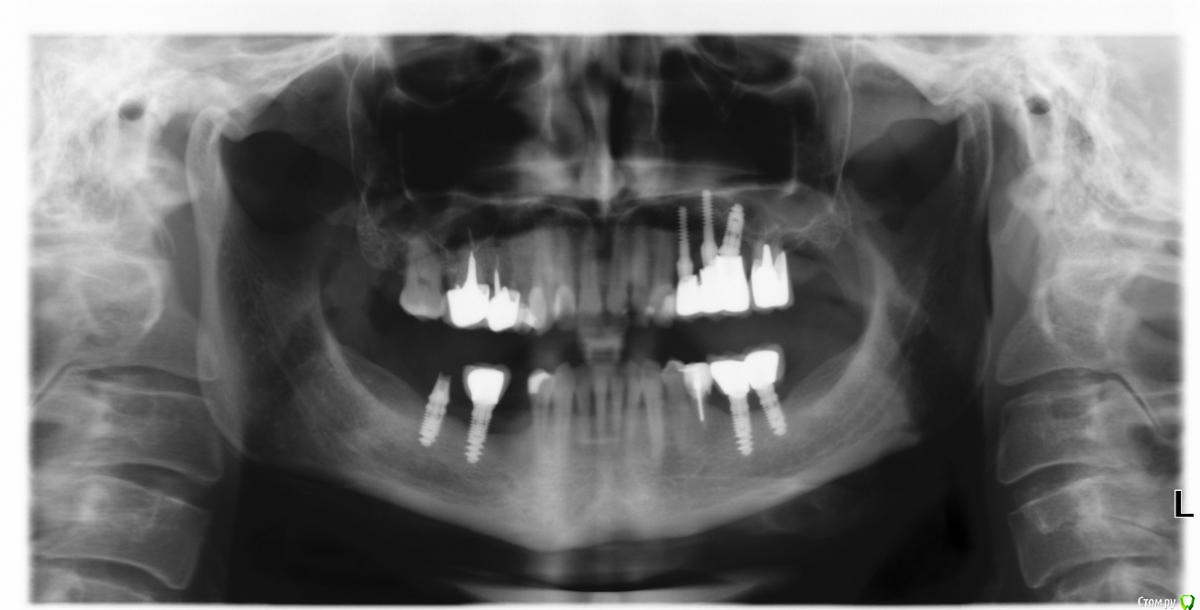

Татьяна_2010 Опубликовано 4 ноября, 2019 Поделиться Опубликовано 4 ноября, 2019 Уважаемые врачи!Посоветуйте, пожалуйста, что лучше предпринять в области 5 зуба справа внизу. История следующая. В 2011 году поставили за раз 7 имплантов. Три сверху слева (через пол года после синус лифтинга) и по 2 импланта внизу (шестерка и семерка) слева и справа. Так как жевать было нечем, то поставили протез, который крепился за пятые зубы. Через месяц пятерки расшатались. Справа 5-ку пришлось удалить. В 2013 году в районе 5-ки справа было проведено две операции по имплантации. Дважды имплант не прижился. При исследовании микрофлоры верхних дыхательных путей и зева был обнаружен золотистый стафилококк. В 2017 году справа с 7-ки слетела коронка с импланта. Обратно ее не поставили, так как десна просела и предложили консоль. Коронки на 7 и 6 зубе будут держать коронку над 5-м. Я бы очень не хотела использовать этот вариант. До нерва под 5-кой было 8 мм в 2017 году, сейчас возможно меньше. Десна совершенно тонкая (узкий альвеолярный гребень). Можно ли в моем случае нарастить десну и при хороших анализах поставить имплант? Заранее спасибо! Ссылка на комментарий

АнтонТЛТ Опубликовано 4 ноября, 2019 Поделиться Опубликовано 4 ноября, 2019 Имплантат в области 6 зуба по снимку не очень хорошо выглядит. Такое ощущение, что половина его длины не в кости. Не помните что за фирма имплантатов? Ссылка на комментарий

Татьяна_2010 Опубликовано 5 ноября, 2019 Автор Поделиться Опубликовано 5 ноября, 2019 Помню, все 7 имплантов израильской фирмы ARDS. Мне сказали, что они взаимозаменяемы с МИС. Мне предлагали удалить 6, но я на это не хочу идти, так как дважды пятый имплант не приживался... Ссылка на комментарий

Irouil Опубликовано 6 ноября, 2019 Поделиться Опубликовано 6 ноября, 2019 Я бы рассматривал 2 варианта: 1) протезировать эти два имплантата временными коронками, ходить с ними год, затем принимать решение о постоянном протезировании. Состояние тканей вокруг имплантатов не идеальное, но выдержать, скорее всего, нагрузку должны. В таком случае отказаться от имплантации в позицию 5 зуба и ограничить все консолью - разумный вариант, по моему мнению 2) идти на костную пластику и в области 5, и в области уже установленных имплантатов, с их предварительным удалением или без Ссылка на комментарий